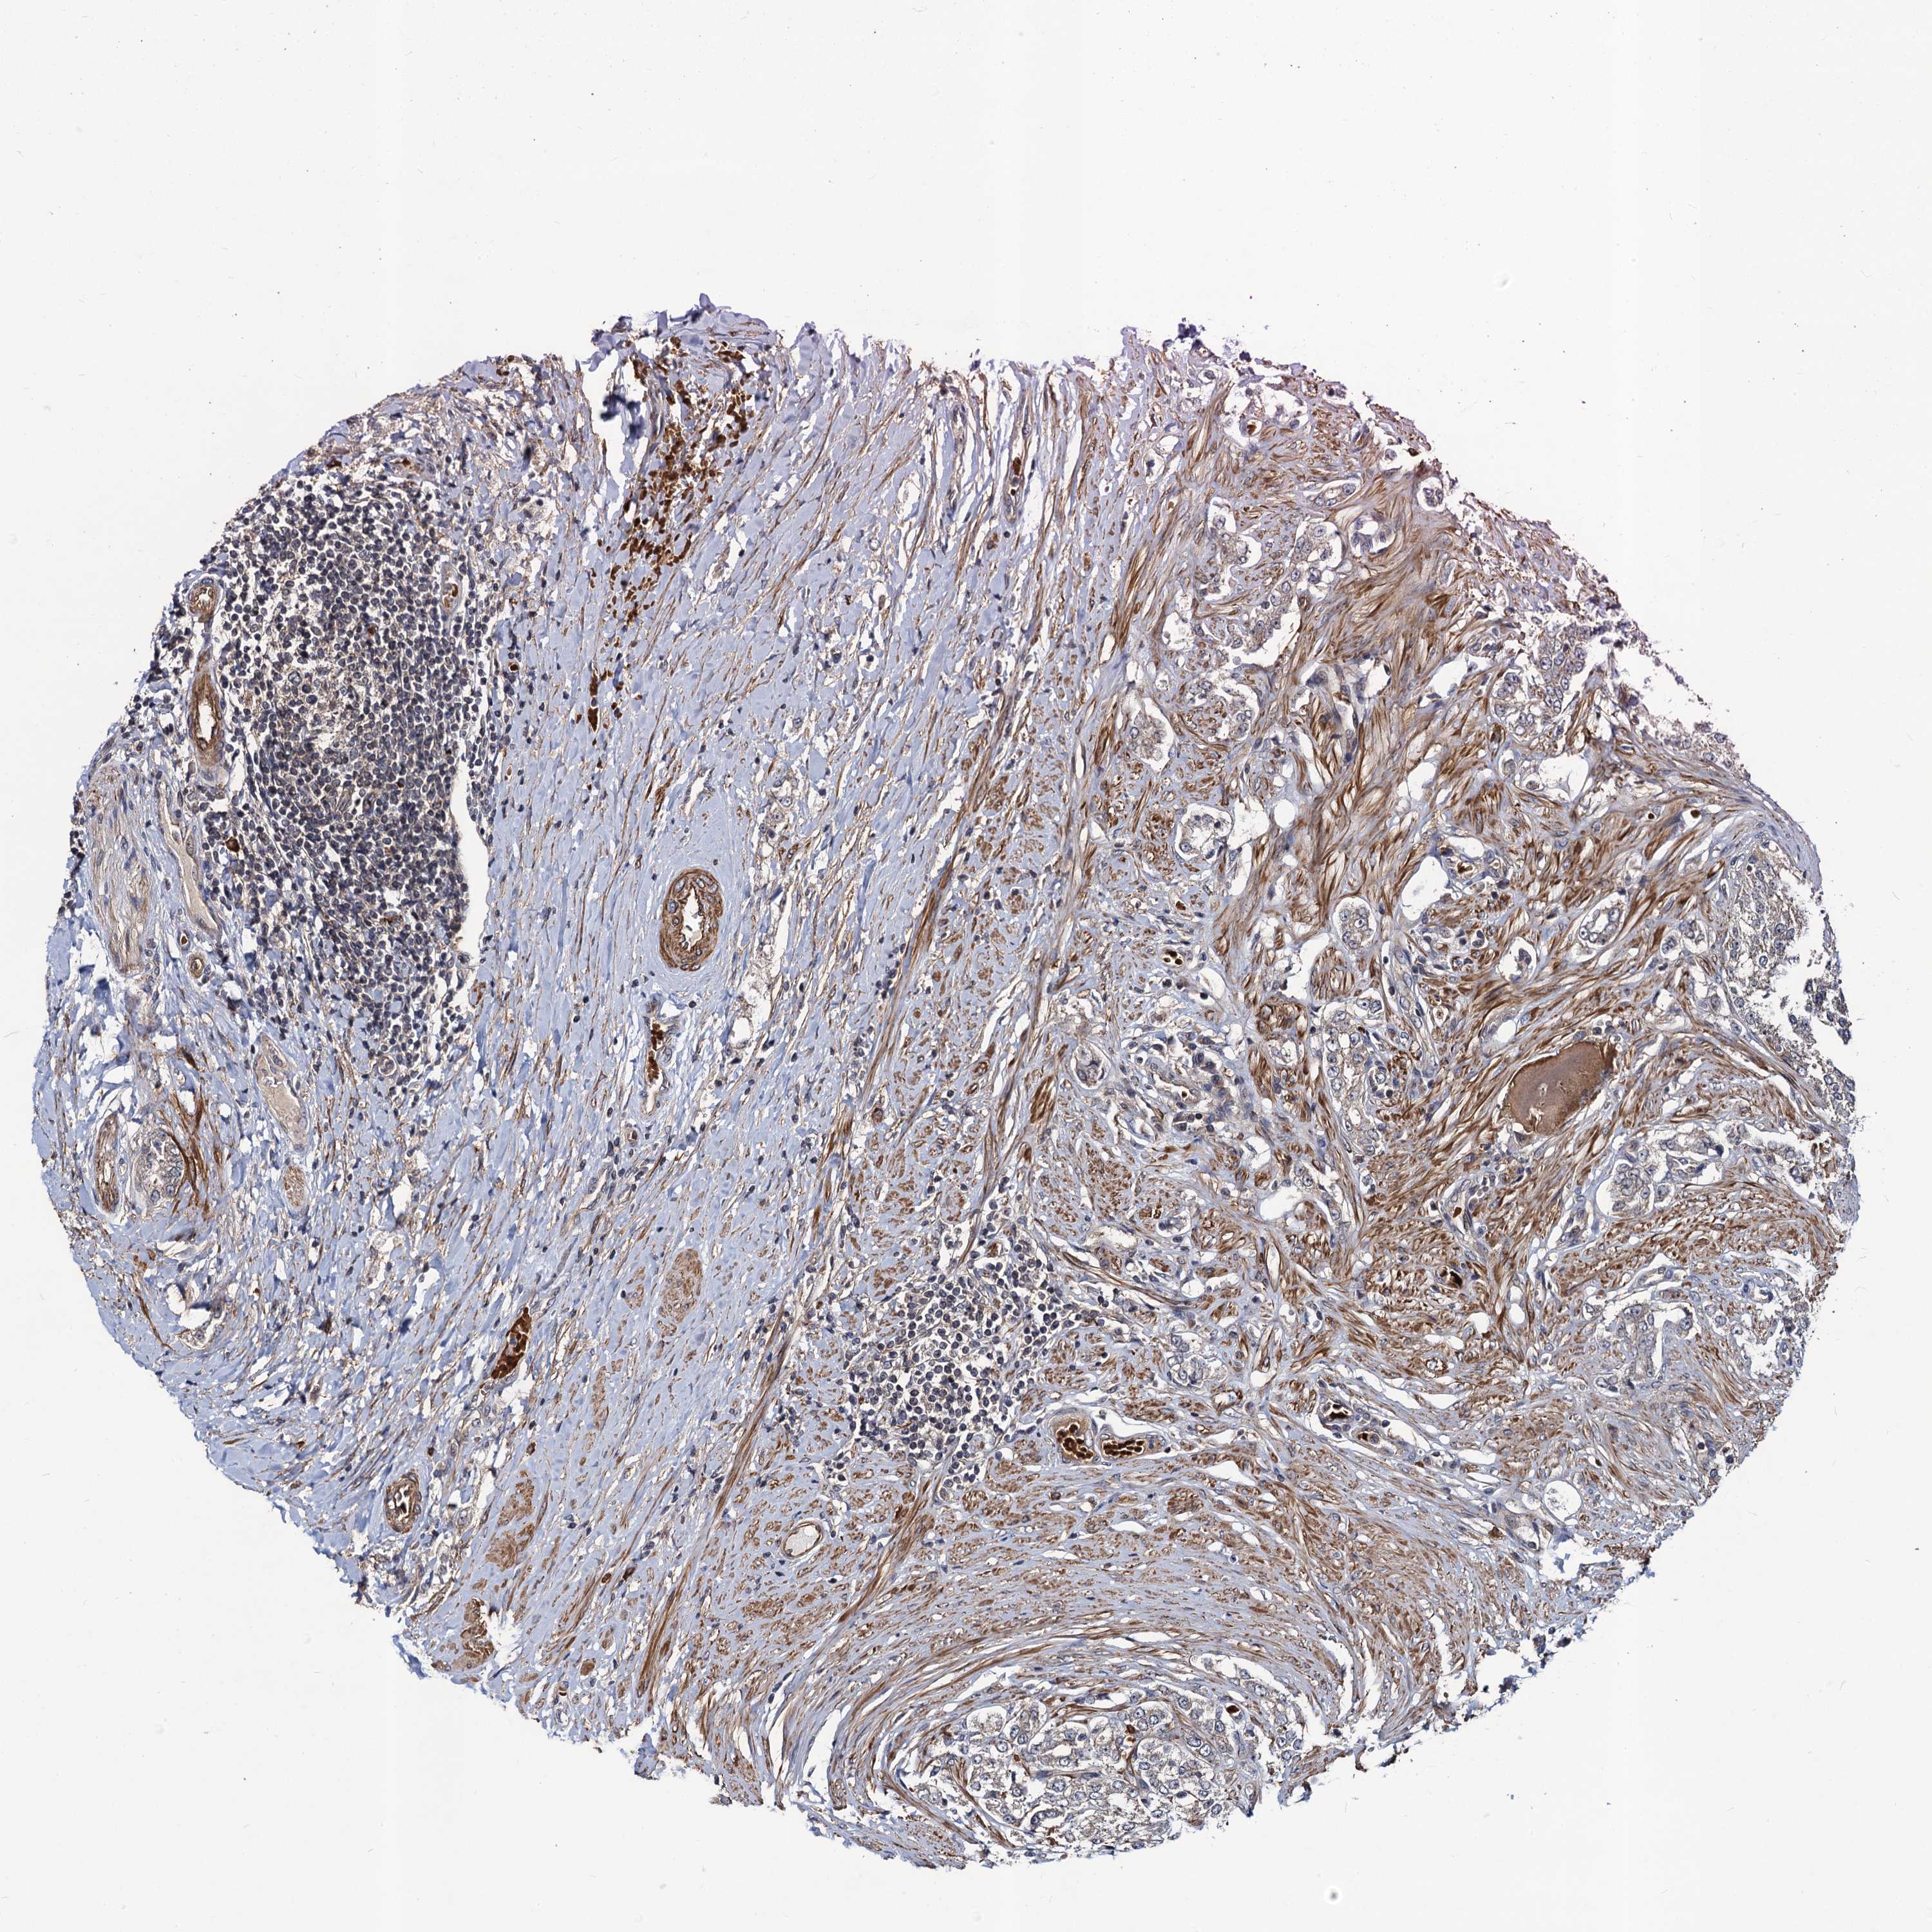

PROSTATE CANCER - Protein expressioni

A mouse-over function shows sample information and annotation data. Click on an image to view it in a full screen mode. Samples can be filtered based on level of antibody staining by selecting one or several of the following categories: high, medium, low and not detected. The assay and annotation is described here.

Antibody stainingi

Antibody staining in the annotated cell types in the current human tissue is reported as not detected, low, medium, or high, based on conventional immunohistochemistry profiling in selected tissues. This score is based on the combination of the staining intensity and fraction of stained cells.

Each image is clickable and will lead to virtual microscopy that enables deeper exploration of all samples and also displays staining intensity scores, fraction scores and subcellular localization as well as patient and tissue information for each sample.

Antibody HPA041507

Antibody HPA041599

Staining

High

Medium

Low

Not detected

Intensity

Strong

Moderate

Weak

Negative

Quantity

>75%

75%-25%

<25%

None

Location

Nuclear

Cytoplasmic/membranous

Cytoplasmic/membranous,nuclear

Adenocarcinoma, High grade

Adenocarcinoma, Low grade

Adenocarcinoma, NOS